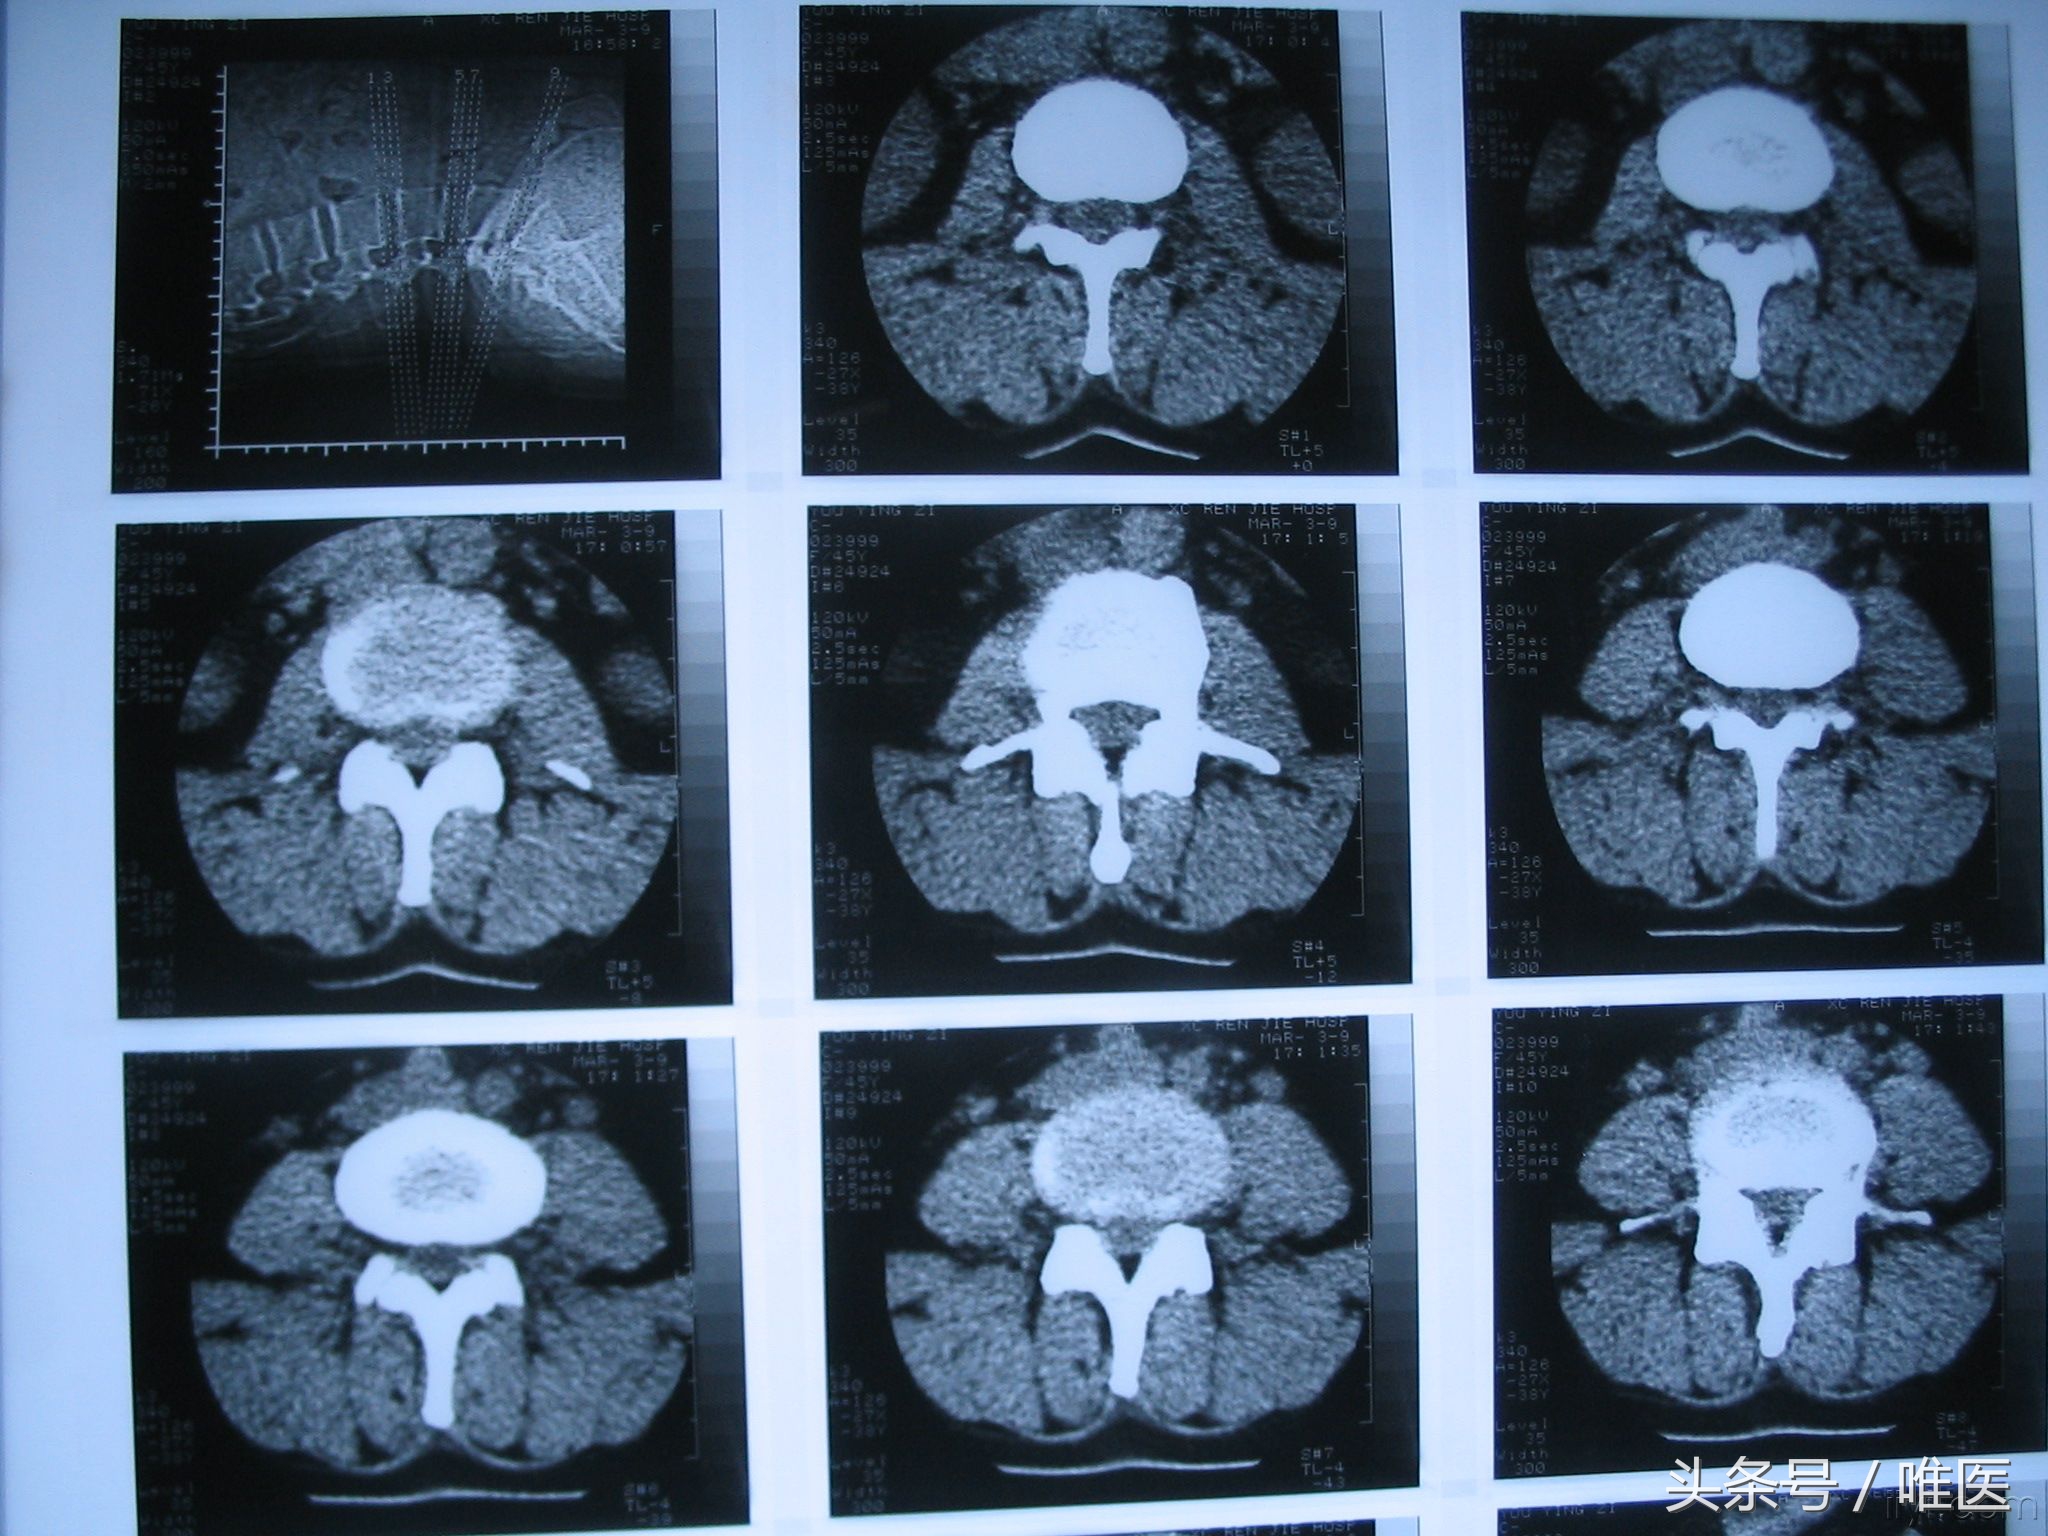

腰椎间盘CT

主要是观察腰椎的横断面,看看间盘是否突出、黄韧带是否肥厚、椎间关节是否增生等一系列引起椎管狭窄的因素。